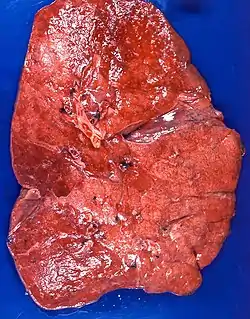

The gross appearance of a lipid pneumonia is that in which there is an ill-defined, pale yellow area on the lung. This yellow appearance explains the colloquial term "golden" pneumonia.[7]